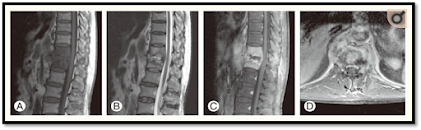

Temuan pencitraan resonansi magnetic (MRI) dari spondilitis tuberkulosis pada wanita 76 tahun. (A)

Gambar sagital berbobot T1 menunjukkan sinyal hipointens pada korpus vertebra T12-L2 dengan

massa epidural dan penyebaran subligamen dari T12 ke L2. (B) Gambar sagital berbobot T2

menunjukkan sinyal hiperintens yang heterogen. (C) Gambar pembobotan sagital T1 yang ditingkatkan

kontras menunjukkan peningkatan heterogen dari badan vertebral T12-L2. (D) Gambar pembobotan

T1 yang ditingkatkan kontras aksial menunjukkan peningkatan abnormal paraspinal dan lesi seperti

abses paraspinal dengan dinding tebal perifer yang disempurnakan dengan baik.